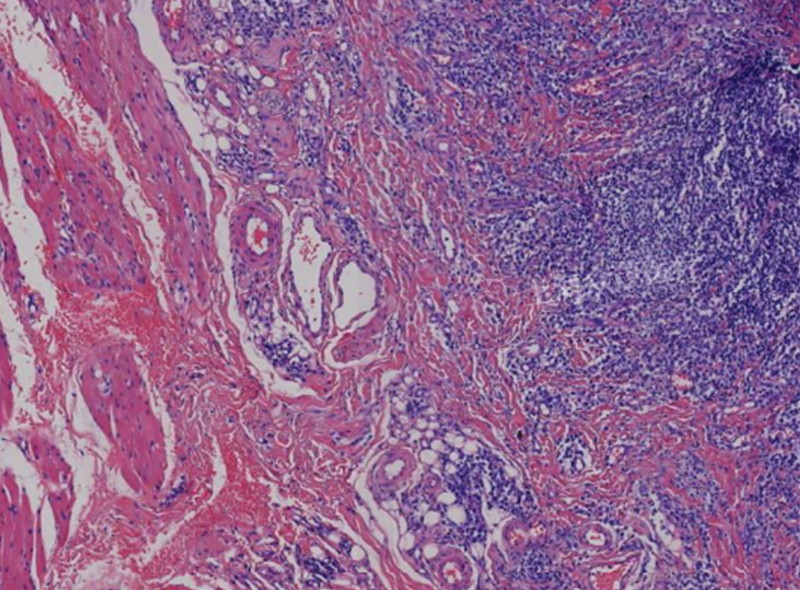

肺出血性梗死